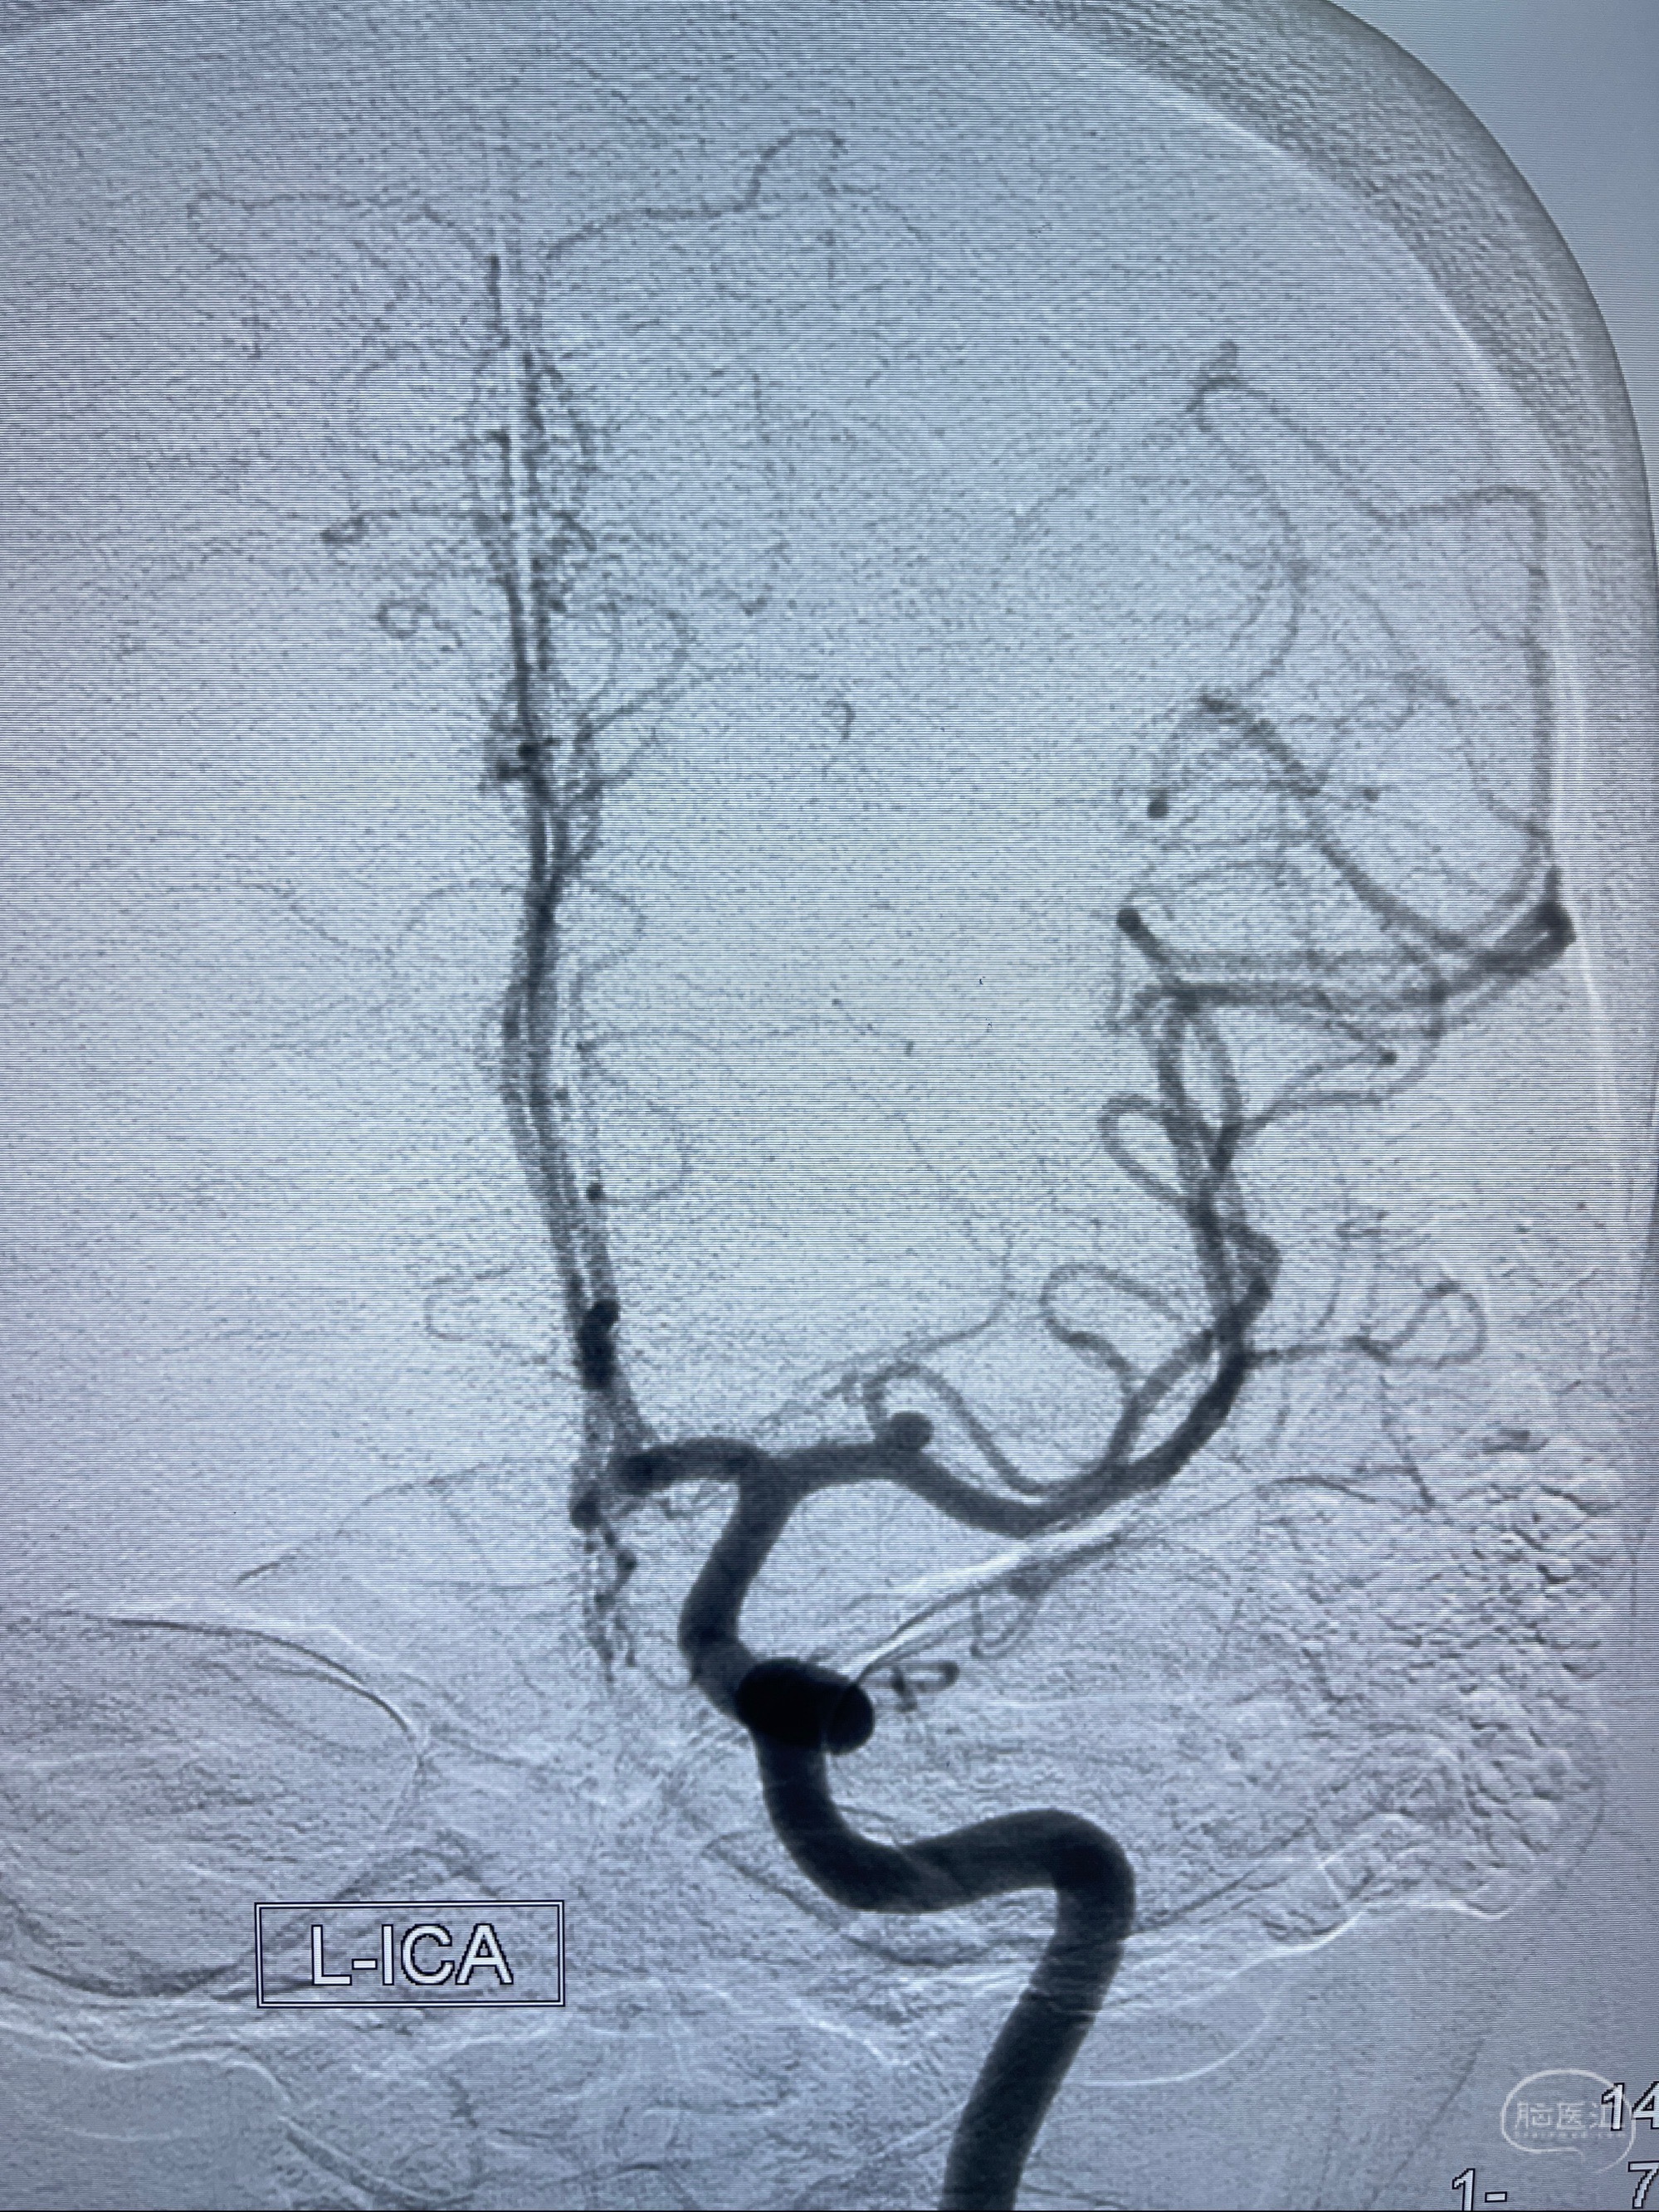

2023-08-14DSA:

左侧大脑中动脉动脉瘤,约2.6-2.8-3.4-2mm大小(瘤颈部、瘤体部、瘤高)

1.左侧大脑中动脉动脉瘤,约2.6-2.8-3.4-2mm大小(瘤颈部、瘤体部、瘤高)